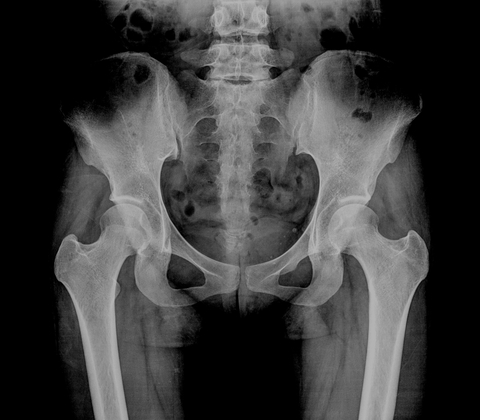

Among our many areas of expertise, hip resurfacing is a particular niche. Unlike a traditional total hip replacement, hip resurfacing aims to preserve more of your natural bone, especially the upper part of the femur (the thigh bone). This approach can provide a more natural movement pattern and is often ideal for active patients who wish to return to a physically demanding lifestyle.

• Bone preservation: Less bone is removed compared to a total hip replacement, which can make future revision surgery easier if ever required.

• Natural joint function: The larger head size of the resurfaced hip more closely mimics natural anatomy, providing better stability and a reduced risk of dislocation.